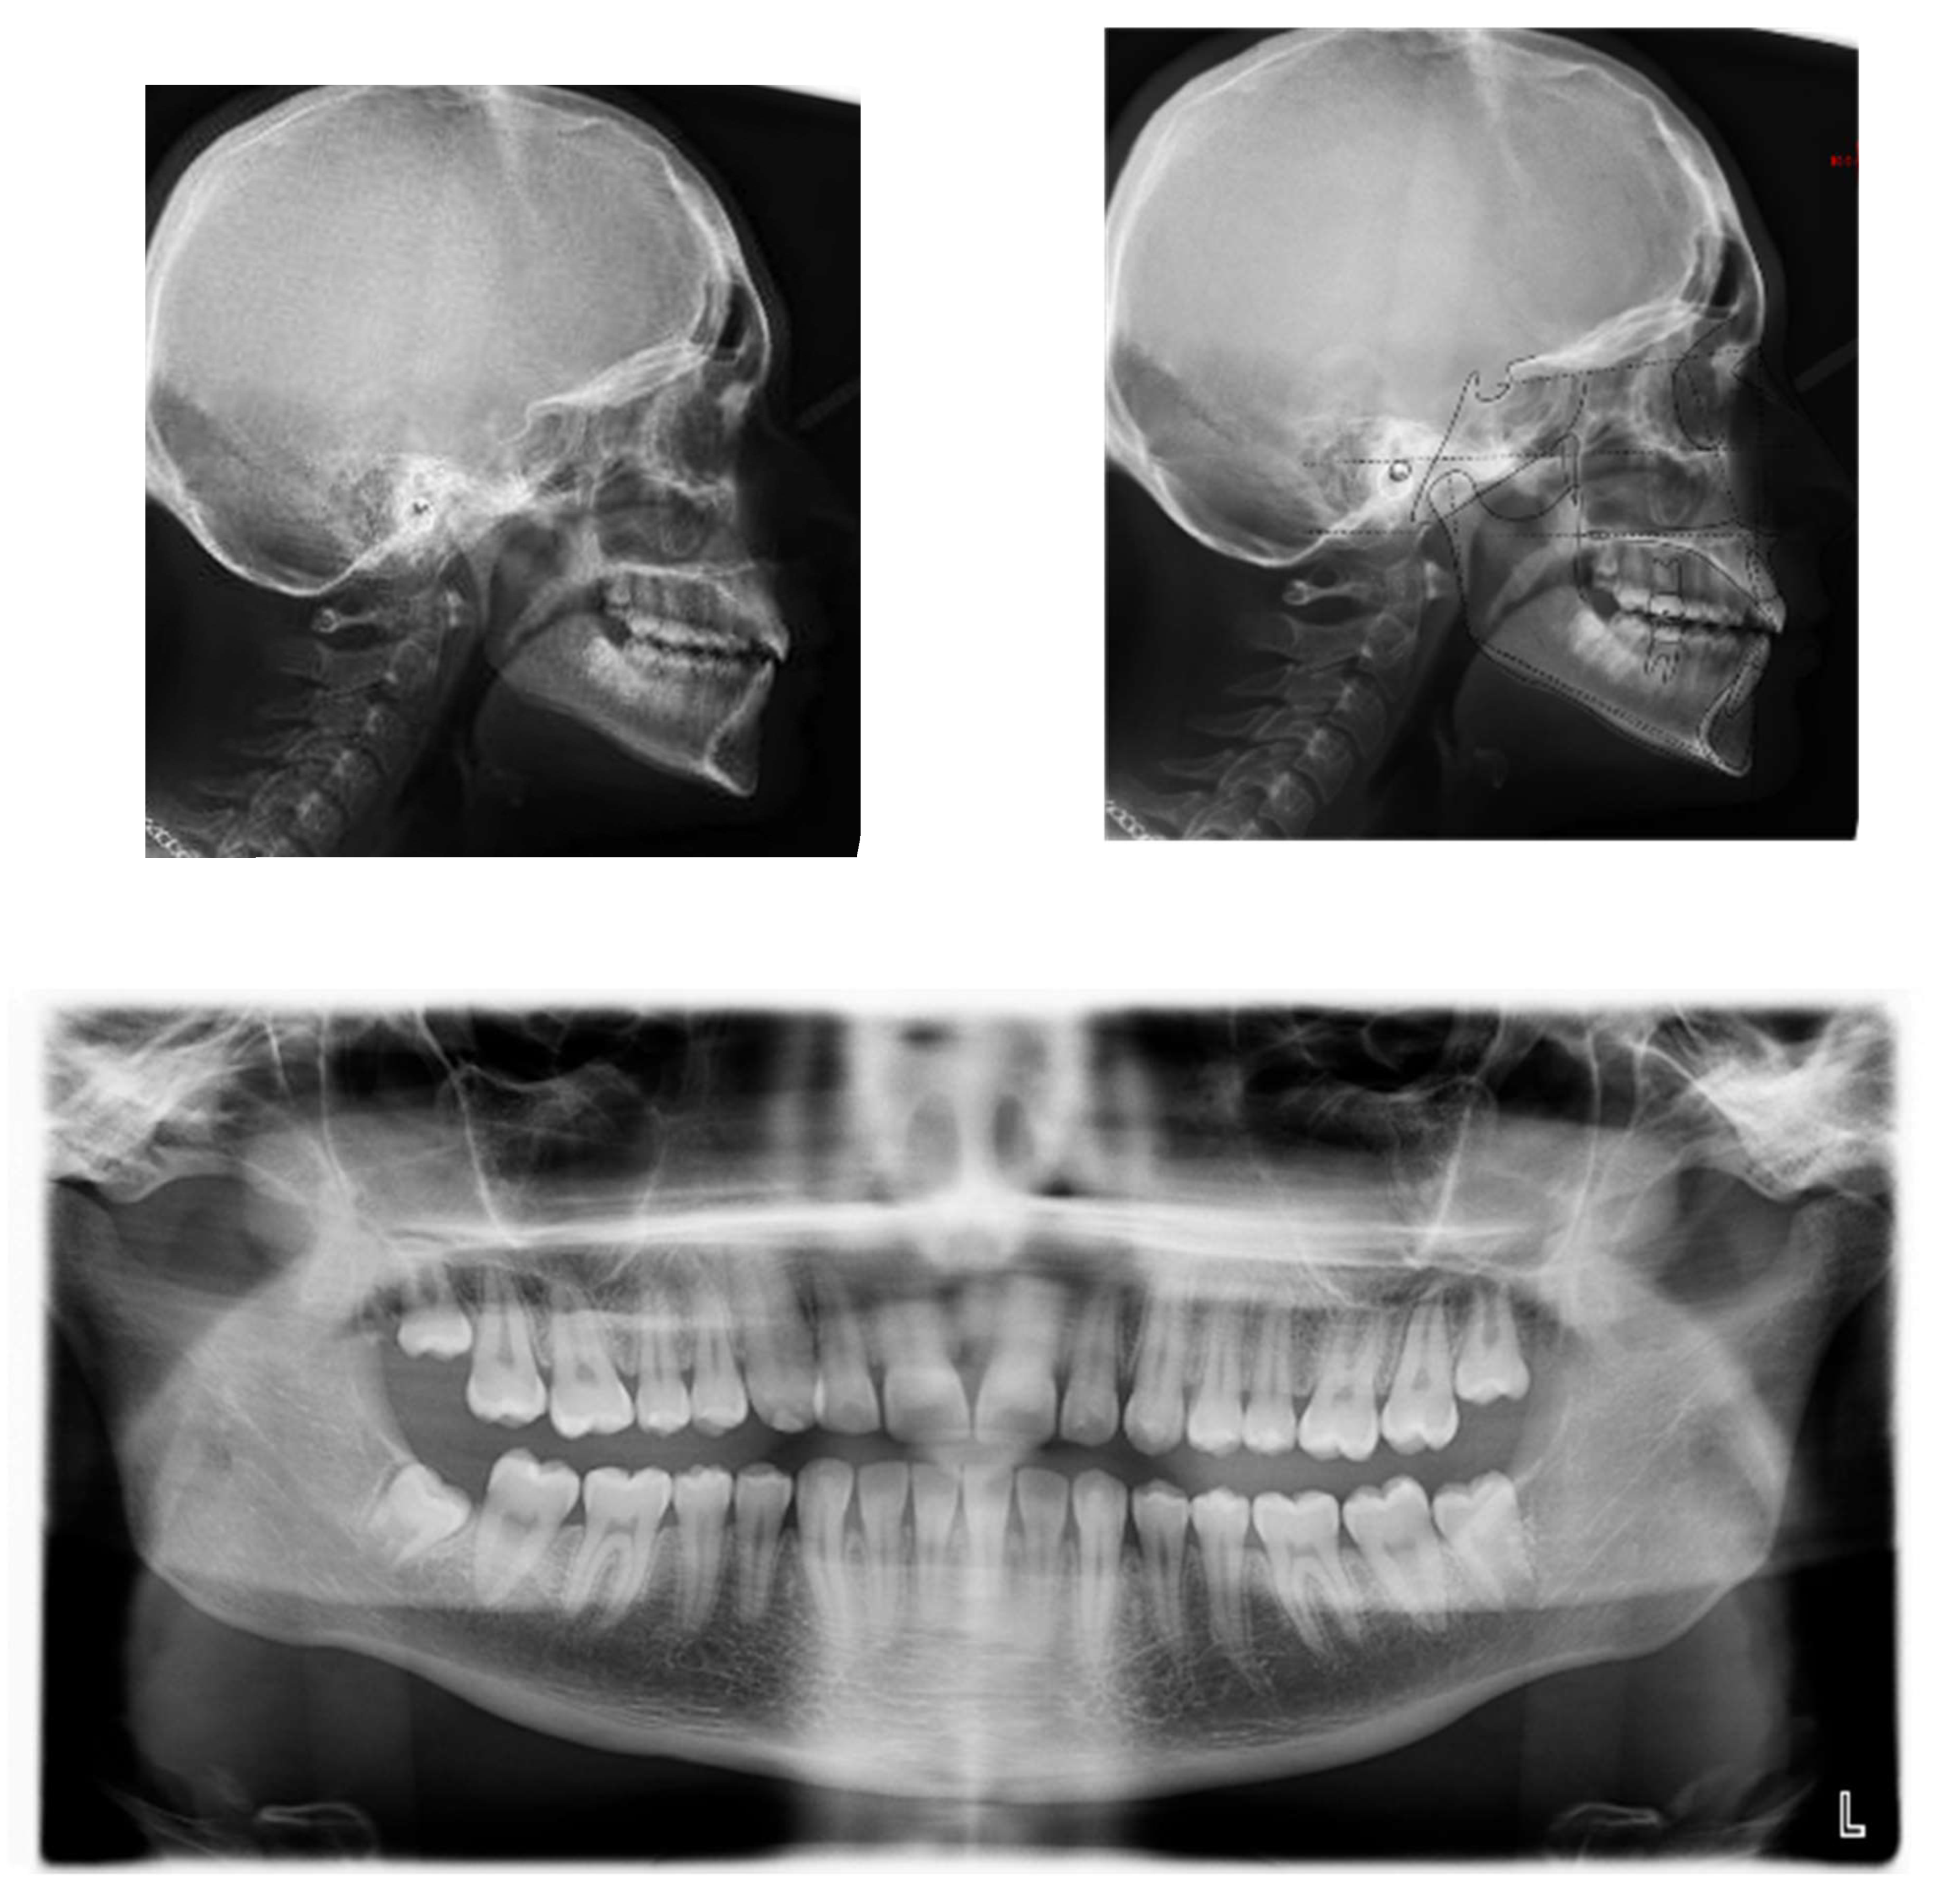

An 18-year-old female patient was referred, complaining of unpleasant smile. She presented good general health and no systemic or congenital diseases. From a frontal view, the patient presented a well-proportioned three-thirds of her face and no evidence of asymmetry. From the lateral view, the profile appeared convex with well-represented nasolabial angle, labiomental sulcus, and lip competence. Intraorally, the patient showed a Class II malocclusion with the molar Class I relationship, edge to edge canine relationship on both sides, increased overjet, overbite, and the retention of the 63. Panoramic, lateral headfilm, and dental cast records were taken (Figure 11).

Figure 11.

An 18-year-old female with dentoskeletal Class II with impacted upper left canine before treatment.

The initial cephalometric analysis showed a skeletal Class I relationship (ANB, +2.6°) and mesodivergent pattern with the proclination of the upper (I/ANS-PNS 118.8°) and lower (i/GoGn:102.2°) incisors. All the radiographic findings, the age of the patient, the prolonged deciduous retention, and the risk of root resorption of the adjacent tooth, led clinicians to conclude that the permanent canine would not erupt properly without intervention (Table 2).

The position of the impacted canine showed an alpha angle of 58° and the Ericson and Kurol II sector classification. No clinical symptoms on articular examination were detected (Figure 12).

Figure 12.

Pre-treatment panoramic X-ray with the evaluation of alpha angle and sector according to the Ericson and Kurol classification.